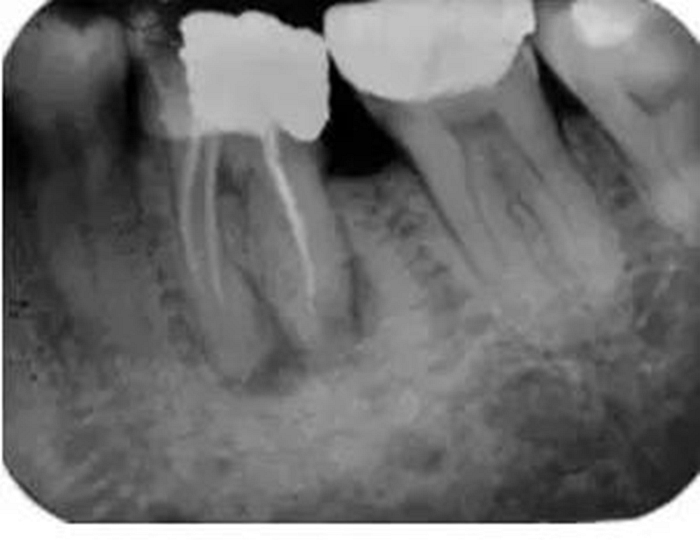

如果根管內(nèi)有樁、折斷的器械或根充物,那么該患牙的治療難度就會(huì)增加(圖3)。樁能否從根管內(nèi)取出取決于樁的大小和形態(tài)。如果根管內(nèi)的折斷的器械位于根尖三分之一和彎曲根的根方,將折斷器械取出來的難度要比在冠方的更困難。